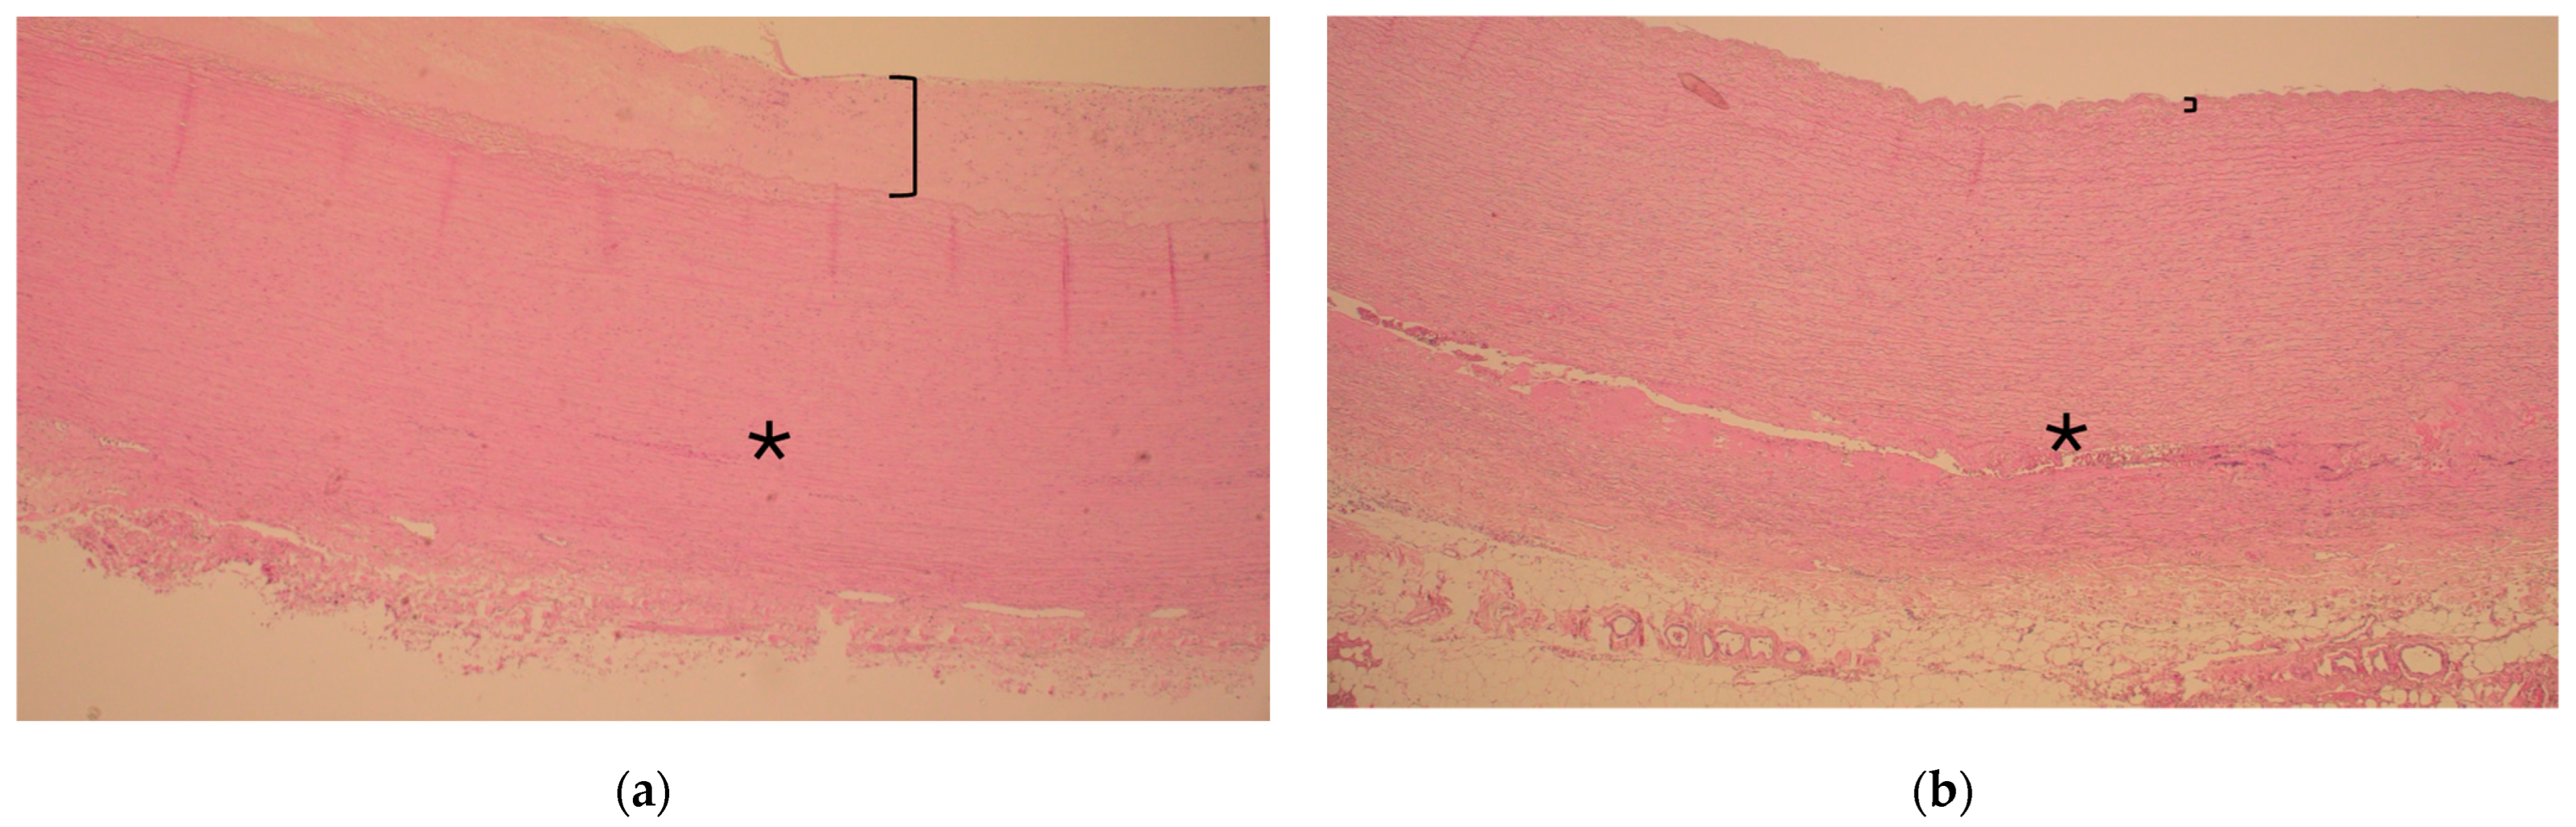

There were no major differences in the histopathology of the aortic wall in patients with or without diabetes as the resected ascending aorta had experienced degeneration but seldom inflammation. However, ascending aorta atherosclerosis was more severe in patients with diabetes mellitus as compared to those without (0.8 vs. 0.3, respectively, p = 0.009), as shown in Table 3 and Figure 1 and Figure 2.

Representative histology of ascending aorta in the vicinity of the sinotubular junction during acute type A aortic dissection in a patient with and without diabetes ((a) and (b), respectively). Note the thickness of the intima layer (bracket) representing atherosclerosis and consistent media layer without extension of dissection (asterisk *) in (a). In contrast, note the clear continuation of the dissection tear inside the media layer (asterisk *) and slim intima layer without atherosclerosis (bracket) in (b). Hematoxylin and eosin, 40× magnification.